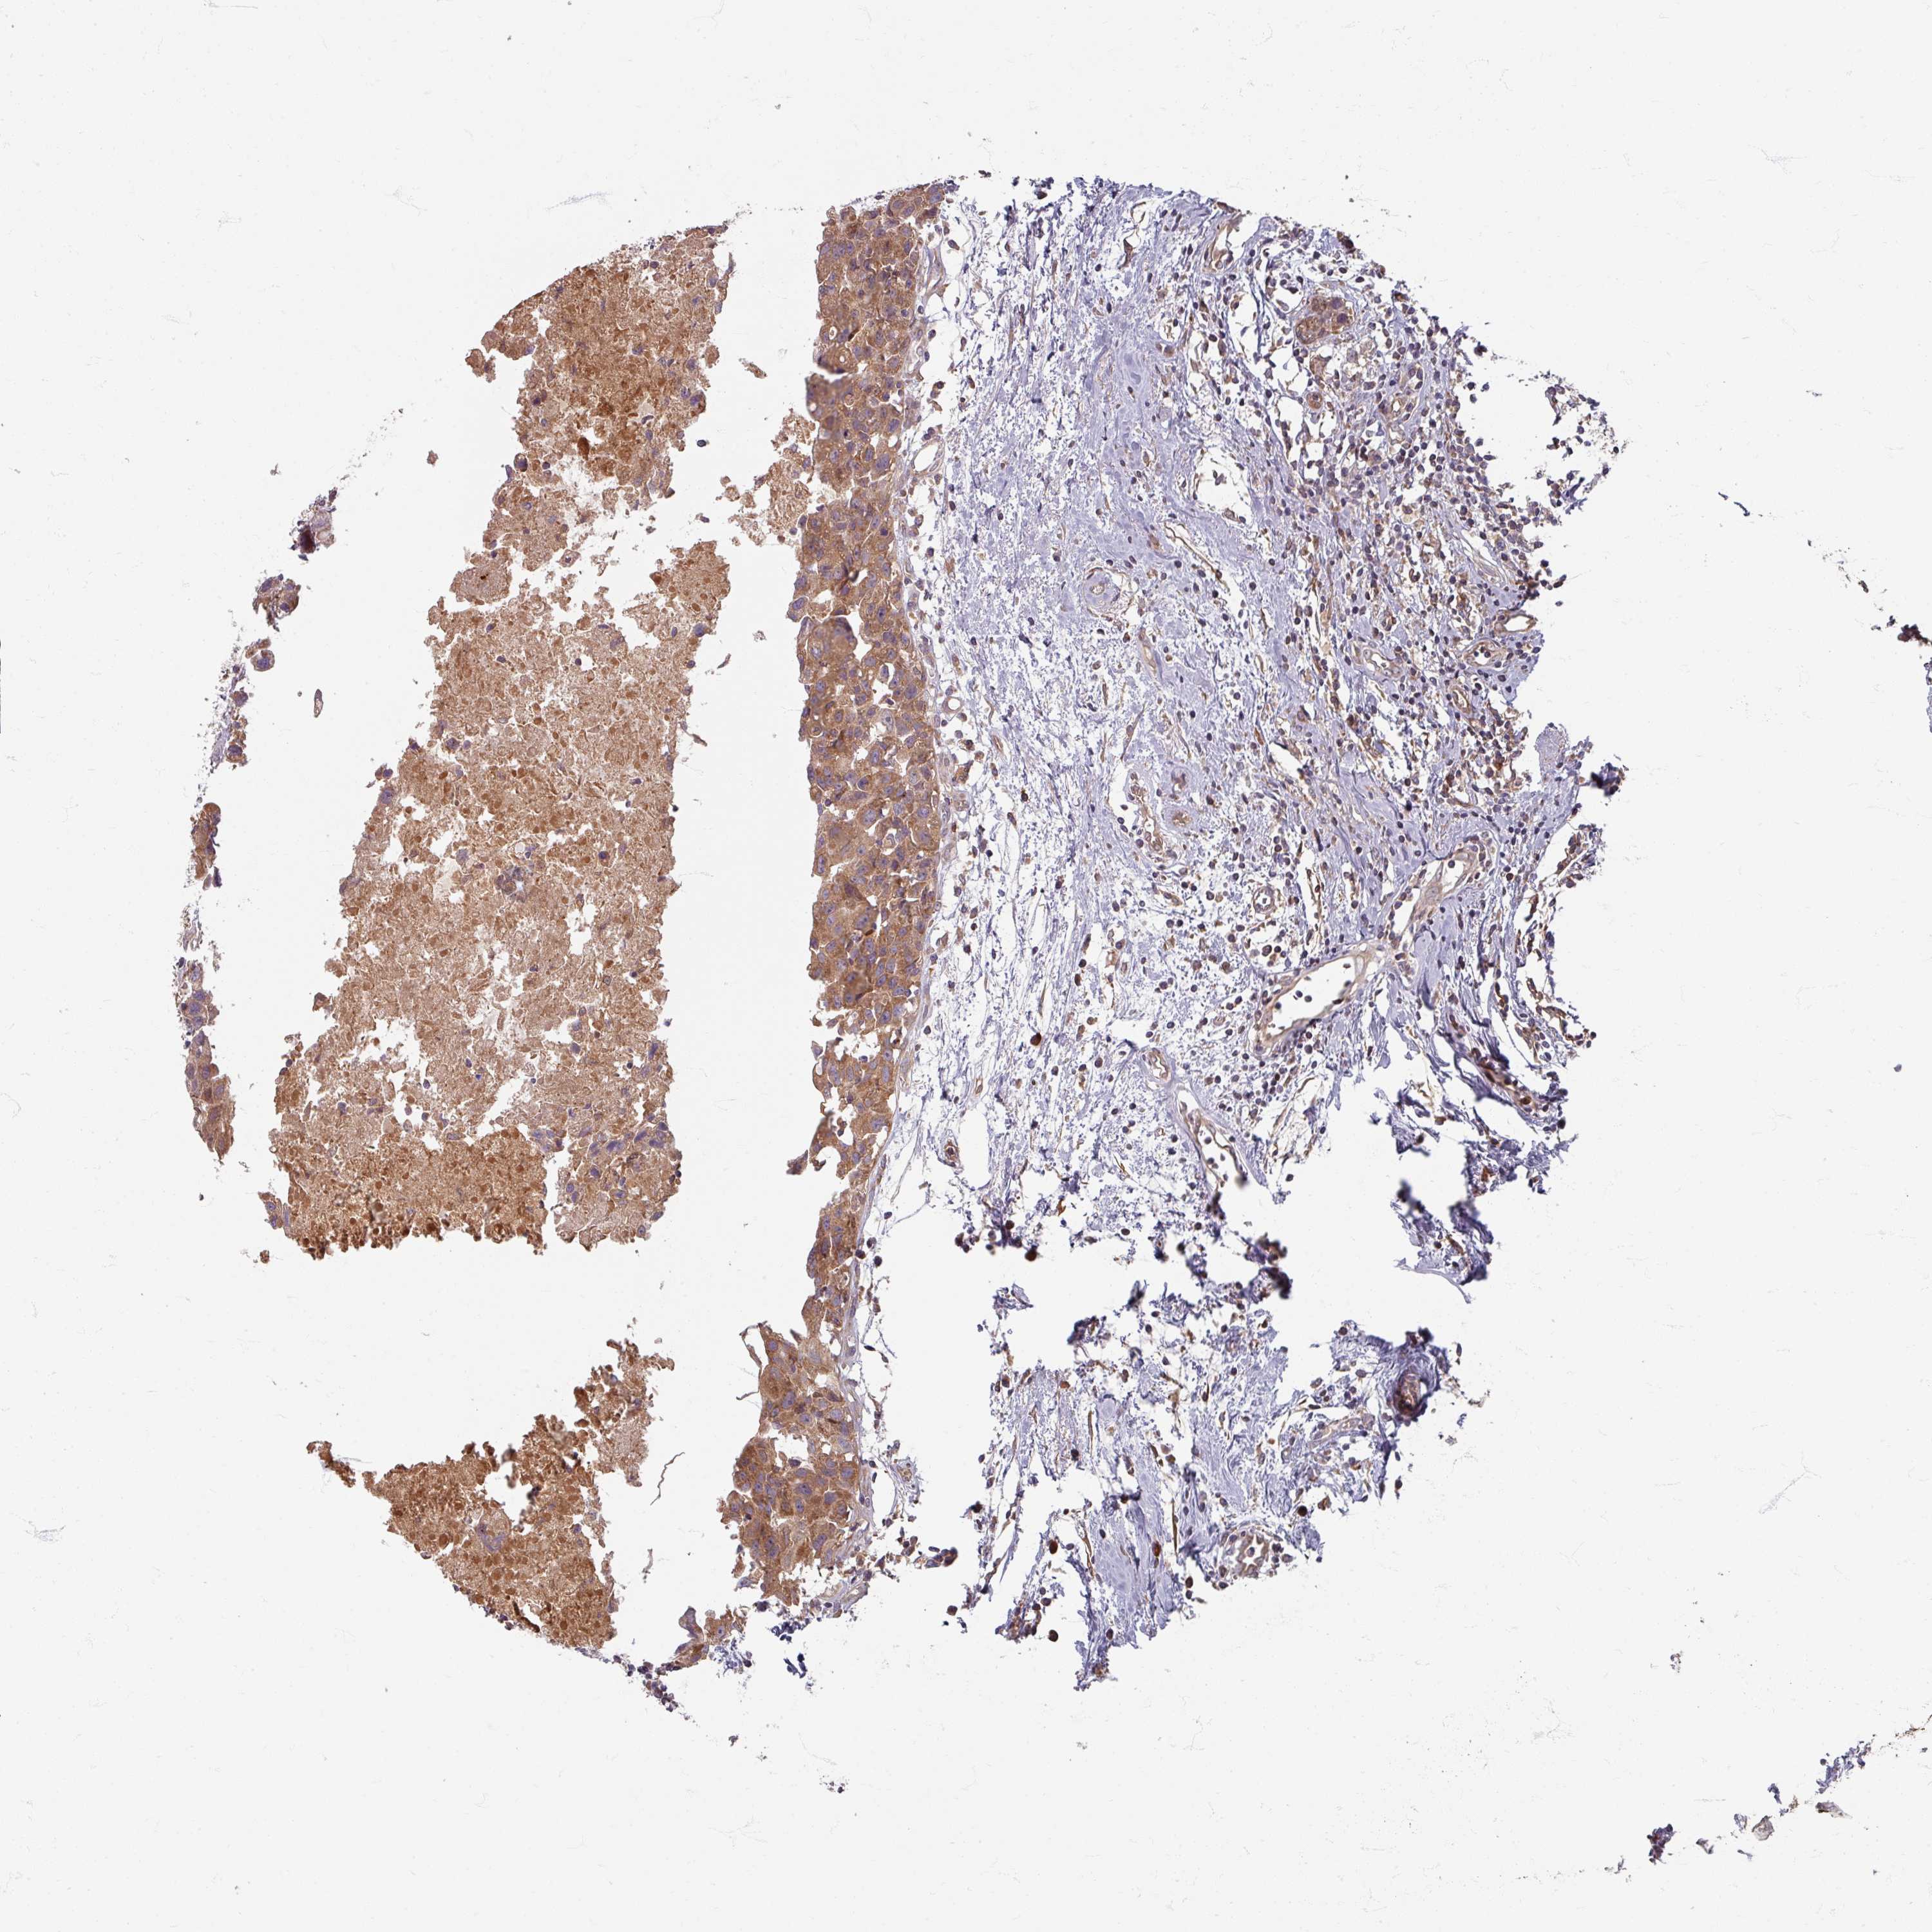

CANCER BREAST CANCER Show tissue menu

BRCA TCGA BRCA VALIDATION PROTEIN EXPRESSION